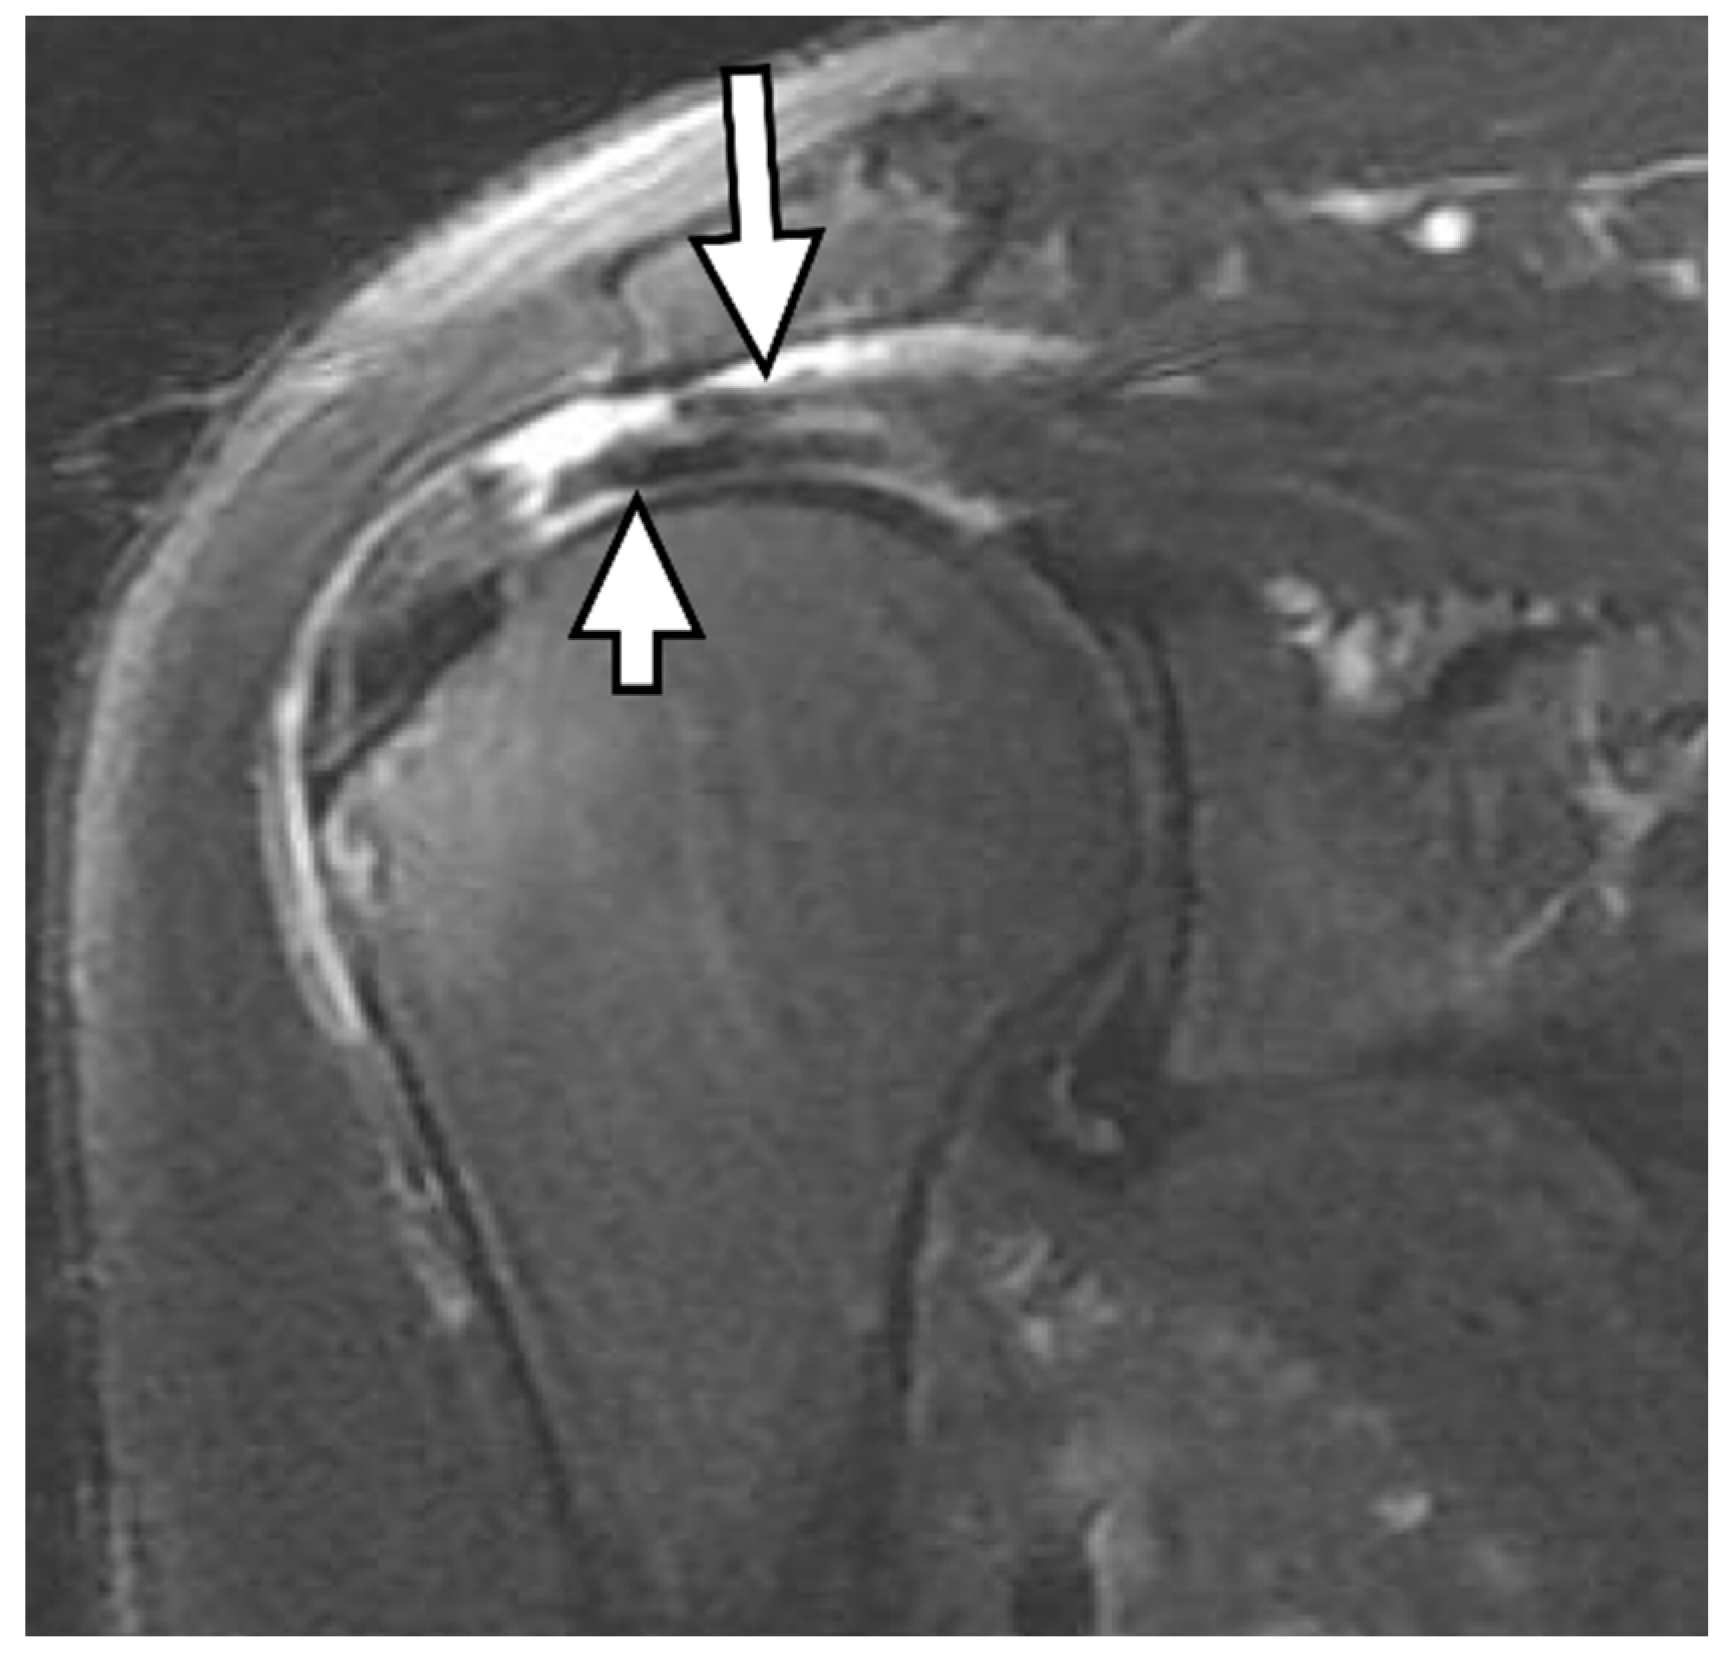

4. Radiologic Definition and Classification Using MRI

5. Radiologic Diagnosis of Delaminated Tears Using MRI